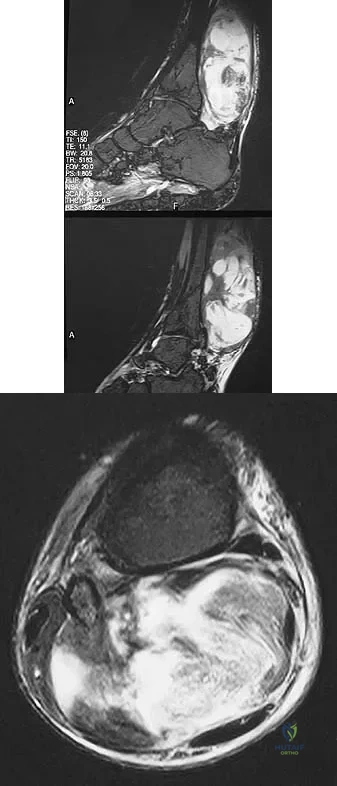

Question 55

Figures 13a and 13b show the MRI scans of a 70-year-old patient who has a posterior calf mass. Examination reveals that the mass extends to the midcalf level. A biopsy specimen reveals a high-grade soft-tissue sarcoma. Metastatic work-up shows no lesions. Management should consist of

Explanation